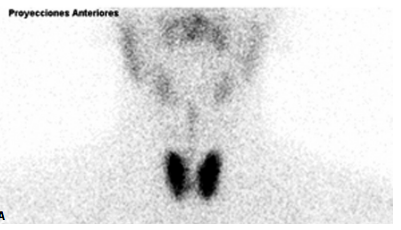

GAMMAGRAFÍA TIROIDEA (sobre Graves)

La gammagrafía con yodo radiactivo o con tecnecio está indicada cuando el diagnóstico es dudoso (exceptuando el periodo de gestación, en el que está contraindicada) y se quiere confirmar el diagnóstico. El rastreo muestra una captación gammagráfica difusa y aumentada